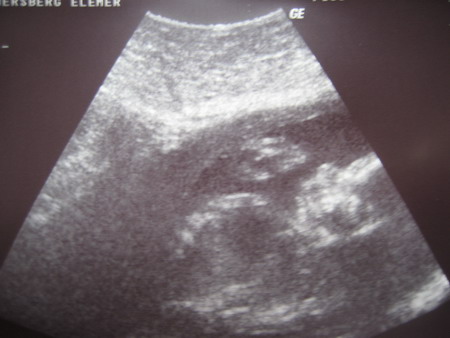

Kiváncsi vagyok, mit mond majd a dokid! De nem lesz ám semmi baj a szülésnél, jó kezekben leszel, meglátod!